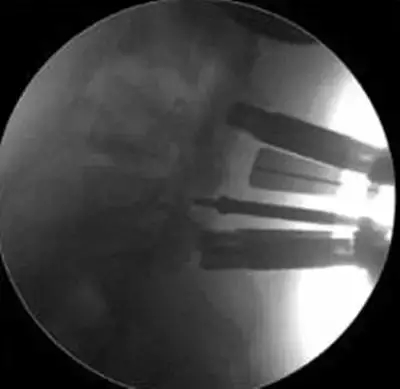

劉志安副院長所說的“微創(chuàng)小切口”就是通道下髓核摘除植骨融合經皮內固定術。其原理就是利用MIS-TLIF技術微創(chuàng)治療腰椎疾病,不但能達到開放手術的效果,且切口及創(chuàng)傷為開放切口的1/3,術中出血量少,患者術后可以恢復更快。

劉志安副院長將具體的手術過程向朱先生做了介紹,朱先生也同意了這個“微創(chuàng)小切口”手術。于是在術前的精心準備之后,劉志安副院長協(xié)同其他醫(yī)護人員為朱先生進行了手術。術后,朱先生的切口愈合良好,腰部疼痛消失,小腿麻木感也漸漸緩解。“手術后傷口略微有點痛,現(xiàn)在已經完全不痛了,這種輕松的感覺已經好久沒有了,真是萬分感謝劉院長。”在病房內,一臉笑容的朱先生如是說。

據(jù)劉院長介紹,MIS-TLIF技術是經椎旁肌間隙入路運用脊柱內鏡或專用通道行腰椎間盤切除、椎管減壓、植骨內固定術,是一項應用廣泛、技術成熟的脊柱微創(chuàng)手術方法。本技術可以完成與傳統(tǒng)手術完全相同的椎間盤切除、椎間植骨融合內固定等操作。手術切口一般3-5厘米,本手術方式可有效避免傳統(tǒng)手術對腰背肌肉的損傷,患者術后腰背部疼痛輕、恢復快,手術效果優(yōu)于傳統(tǒng)手術,治療后1-3天即可下床活動。本技術適于大部分的腰椎間盤突出癥、腰椎管狹窄癥、腰椎滑脫癥等。